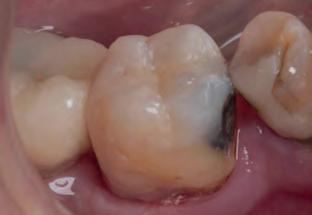

Periapical X-ray confirmed the findings of the clinical examination and root caries was also detected in the distal root of tooth #46, which answered positively to the sensitivity test (Fig.1-2).

The treatment plan began with a focus on returning the patient to adequate periodontal health. In a subsequent session, with improved condition of the periodontium, the restoration of tooth #46 was performed. Under block anesthesia of right inferior alveolar nerve and rubber dam isolation, the amalgam restoration was completely removed and access to the caries cavity obtained (Fig. 3-5). Despite the proximity to the pulp tissue, no exposure occurred, and the class II cavity was fully restored with Biodentine™ (Fig. 6-8).

Fig. 1: Initial clinical situation.

Fig. 4: Septomatrix in position.

Fig. 2: Initial X-ray.

Fig. 5: Cavity deep.

Fig. 3: Class II cavity prepared.

Fig. 6: Biodentine™ applied in a Bio Bulk-Fill approach.